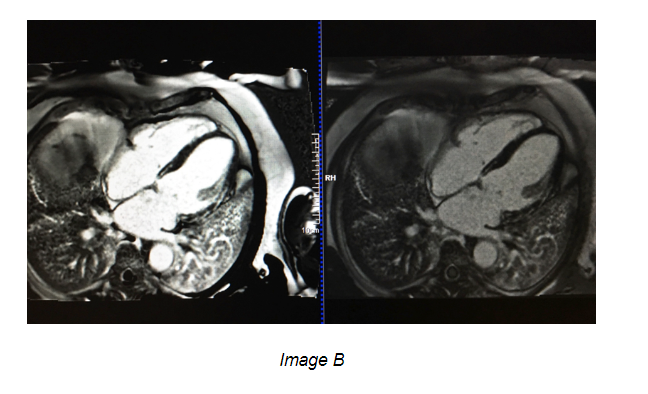

Late Gadolinium Enhancement (LGE) Imaging is an integral part of the Cardiac Imaging exam. LGE imaging helps define whether a myocardial injury is ischemic or non-ischemic. The difficult task is choosing the correct TI value. To do this, you should run a TI scout. This is acquired in a mid slice Short axis position, where the left ventricle is in a round position. The time to acquire the TI scout is 6-10 minutes after the gadolinium injection (dose of 0.1mmol/kg, or 1ml/kg bodyweight, depending on the contrast used). The correct TI is when the myocardium is as black as the lung field. The TI scout acquires an image usually every 60-80 ms to demonstrate the myocardium (Image A). Typically, the blood pool will be nulled before the healthy myocardium. Choose the value after the blood pool appears black, and when the myocardium is completely black. This allows for adequate suppression of the signal from the healthy myocardium. Damaged, or scarred, myocardium appears bright white against the healthy suppressed heart tissue (Image B). The LGE images should match the Long axis and Short axis images, to allow accurate diagnosis and evaluation.